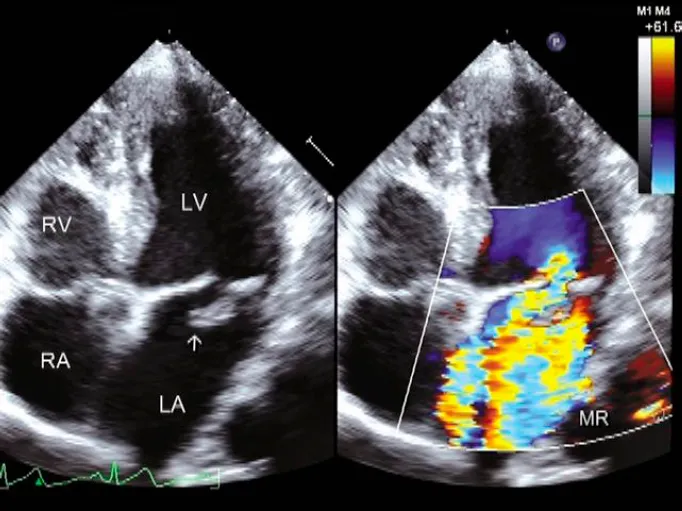

Mitral Regurgitation (MR): Valve won't close

- Etiology: Mitral valve prolapse, ischemic heart disease, infective endocarditis.

- Auscultation: Holosystolic (pansystolic) murmur, high-pitched, loudest at the apex, radiating to the axilla.

- Pathophysiology: LA & LV volume overload → LV dilation & failure.

⭐ In acute MR (e.g., papillary muscle rupture post-MI), the sudden volume load on a normal-sized LA/LV leads to prominent pulmonary edema and hypotension.